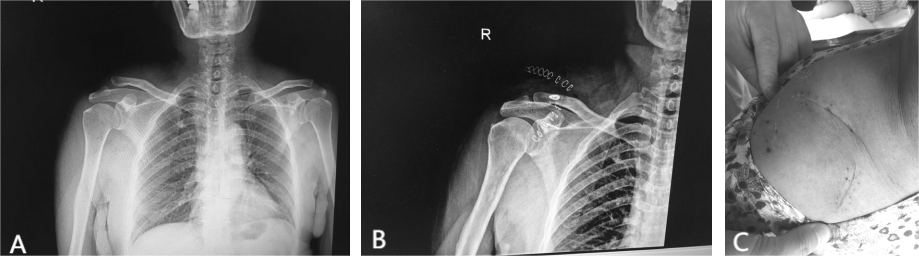

患者经臂丛神经阻滞麻醉成功后,取仰卧位,患肩部垫高,常规消毒,铺巾,取患侧锁骨外段切口,切开皮肤、皮下组织、深筋膜,显露患侧肩锁关节。术中见肩锁关节脱位、锁骨外侧端向前向上移位,肩锁、喙锁韧带断裂。清除血肿,于距离锁骨远端2cm、4cm处背侧钻孔,背侧放置2个锁扣袢钢板,其高强度拉线绕过喙突基底部,复位肩锁关节,克氏针临时固定,透视见肩锁关节复位满意,收紧锁扣袢钢板上的高强度线并打结,拔除克氏针,修补肩锁关节,生理盐水冲洗创口,逐层缝合(图2)。

图2 A为术前患肩X线片,B为术后患肩X线片,C为术后伤口。